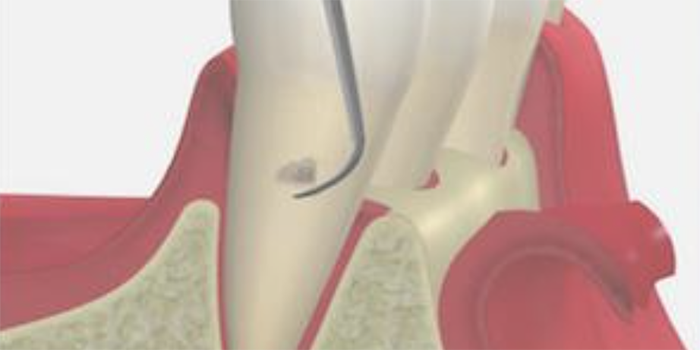

4. 歯周ポケット掻爬術

歯ぐきの内側の炎症をおこしている組織を取り除く処置です。

麻酔の効いている状態で行うため、治療中の痛みはほとんどありません。

内側からの炎症改善を目的としており、清潔になった歯の根に歯ぐきが付着し、汚れが溜まりにくい環境を作ることができます。